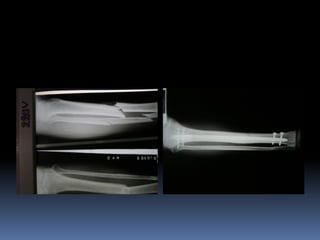

 Tại SaoTôi Phải Cố Định Xương Gãy? Bằng Cách Nào?

 Tại SaoTôi Phải Cố Định Xương Gãy? Bằng

Cách Nào?

 Tại SaoTôiPhải Cố Định Xương Gãy? Bằng Cách Nào?